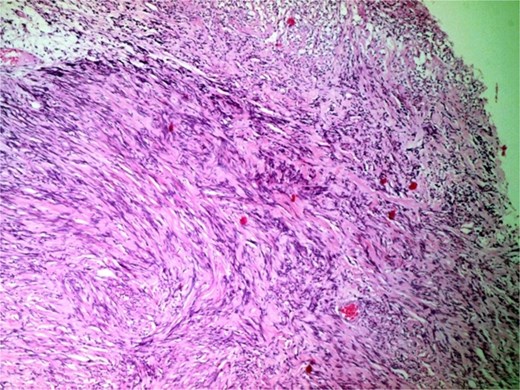

A 44-year-old right-handed woman presented with a two-month history of headache and blurred vision. Her medical history included hypertension and type 1 diabetes mellitus. She reported gradually worsening intermittent headache and bilateral visual blurring, more pronounced in the right eye. Symptoms exacerbated with physical exertion and were unrelieved by analgesics, leading to her referral. Examination revealed a conscious, alert patient with right eye proptosis. Visual acuity was 6/6 (left eye) and 6/9 (right eye). Fundoscopy identified bilateral Grade 3 papilledema. Non-contrast brain CT demonstrated a well-defined, isodense, dural-based extra-axial lesion in the left frontal region with a cystic component, measuring approximately 5.5 × 4.3 × 4.2 cm. It was associated with mild perilesional edema, mass effect, and a subtle contralateral falx shift. The initial impression was an atypical meningioma (Fig. 1). Subsequent MRI confirmed a large, falcine-based lesion that appeared isointense on T1- (Fig. 2) and T2-weighted images, demonstrating intense homogeneous enhancement post-contrast (Fig. 3). Signal voids suggested calcifications. The patient underwent gross total excision via a bilateral frontal craniotomy. The tumor was intradural and extra-axial, elevating the frontal lobe and was easily accessible; therefore, neither neuronavigation nor other intra-operative localization aids were utilized. Intraoperatively, the olfactory tract could not be clearly identified. A gap in the anterior cranial base was noted, but as there was no evidence of dural invasion or cerebrospinal fluid leak, no sealant was required. Gross examination of the resected specimen revealed a well-circumscribed, white nodule. Microscopically, sections showed benign spindle cell proliferation with alternating Antoni A and Antoni B areas (Fig. 4). Antoni A regions displayed nuclear palisading and Verocay bodies (Fig. 5), while Antoni B areas were edematous and myxoid (Fig. 6). No mitotic figures or atypia were seen. The definitive diagnosis was a benign olfactory groove schwannoma, notable given the initial radiological suspicion of meningioma. Her postoperative course was uneventful. A postoperative non-contrast CT brain obtained 48 hours after surgery confirmed gross total resection (Fig. 7). She was discharged with scheduled follow-up to monitor recovery and visual symptoms.

Photomicrograph showing a well-circumscribed, partially encapsulated lesion composed of hypercellular Antoni a areas admixed with myxoid hypocellular Antoni B areas (H&E, ×100).

Definitive diagnosis relies on histopathology and immunohistochemistry. Microscopy revealed the classic biphasic pattern of benign schwannoma with Antoni A and B areas, nuclear palisading, and Verocay bodies, a pattern foundational to diagnosis [4–7, 9, 10]. Immunohistochemistry is crucial for differentiation. The tumor cells showed strong, diffuse S-100 protein positivity [4–7, 9] and were negative for Epithelial Membrane Antigen (EMA), which is typically positive in meningiomas [5–7, 9]. This S100-positive/EMA-negative profile is definitive for schwannoma. Additional markers like SOX-10 [4] or CD57 [5, 9] can further distinguish OGS from other rare tumors.